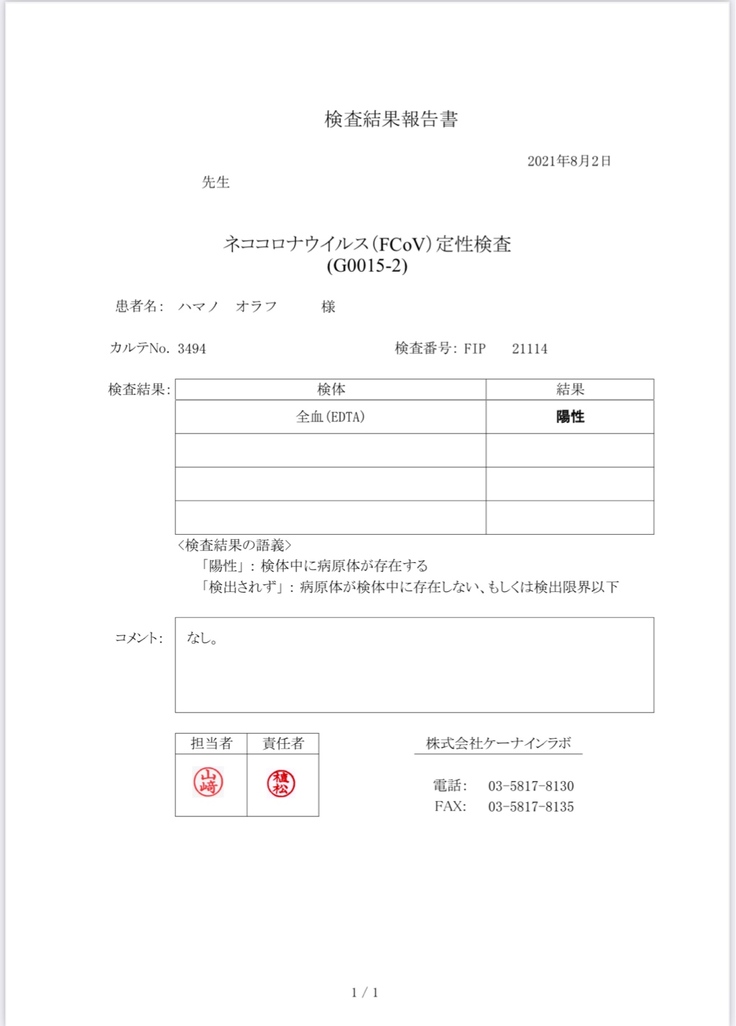

FIP検査結果が出るのは約1週間後です。

8月2日

オラフのFIP陽性の検査結果が出ました。